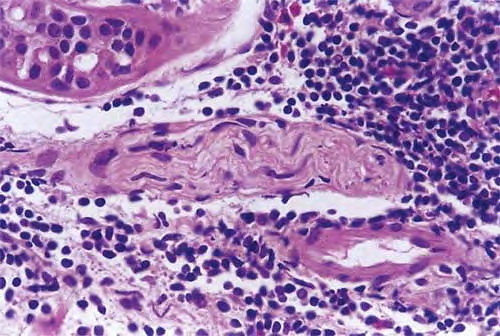

Erythema Chronicum Migrans =الحمامى المزمنة الهاجرة